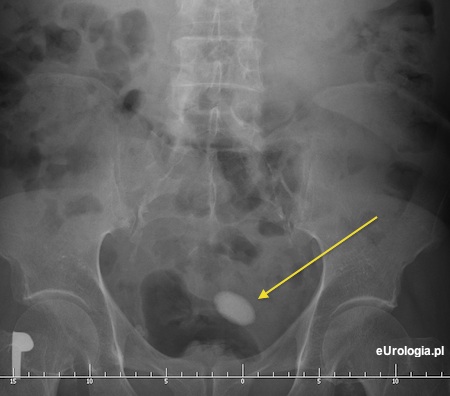

Podstawowym badaniem wykonywanym w celu rozpzoznania kamicy pecherza moczowego jest badanie USG jamy brzusznej. Dodatkowo możliwe jest wykonanie zdjęcia rentgenowskiego nerek i pęcherza. Czasami istnieje konieczność wykonania cystoskopii kiedy badania obrazowe nie dają jasnej odpowiedzi. Kamień wpęcherzu moczowym jest dobrze widoczny w badaniach obrazowych. Poniżej przykłady kamicy pęcherza moczowego w badaniach obrazowych.

Fot. Cień złogu na zdjęciu przeglądowym jamy brzusznej